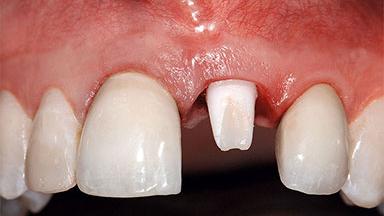

A healthy 37-year-old female patient was referred for a consultation on the replacement of missing tooth 21 with an implant-supported restoration. She stated that several years previously the tooth had been traumatically avulsed following a motor vehicle accident. The tooth was replaced with a three-unit fixed partial denture (FPD) immediately afterwards. Over time, she became disillusioned with the FPD and looked for a different option, including orthodontic therapy. She presented still in her orthodontic appliances, with the pontic sectioned free from the FPD but attached to the archwire. Her orthodontist felt that orthodontic treatment had been successfully completed, but nevertheless referred her before removing the appliances in case adjustments were necessary.

Bone Volume Deficient horizontally, allowing simultaneous augumentation

Soft Tissue Contour and Volume Slightly compromised